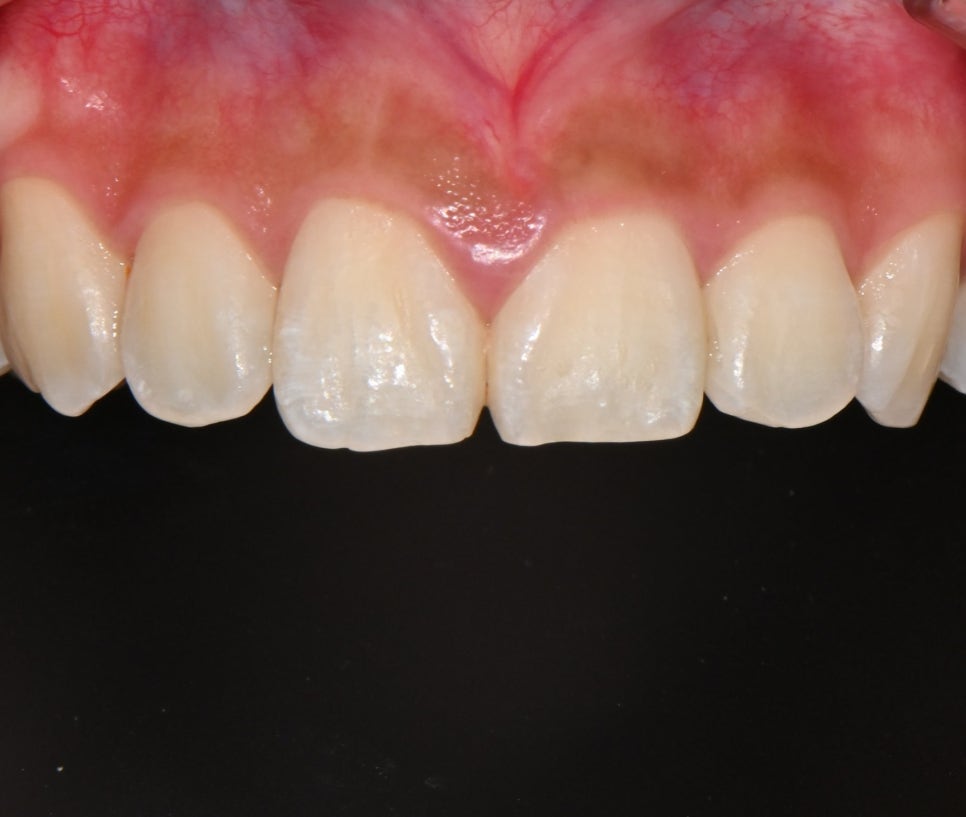

📸 Before

– 어두운 치아 톤

– 살짝 비대칭인 치아 라인